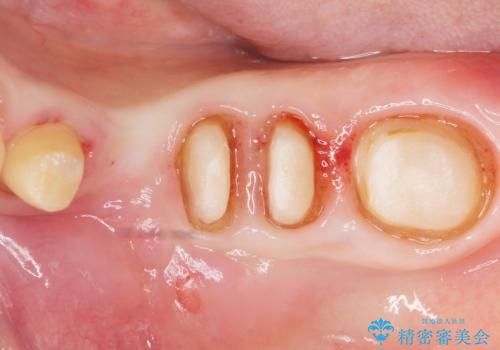

虫歯を丁寧に除去した後に歯根を分割し、骨を削合して健全歯質を露出させる骨外科手術を行いました。

手術後に根管治療を行い、歯肉と骨の治癒を十分に待った後ブリッジによる補綴治療を行いました。